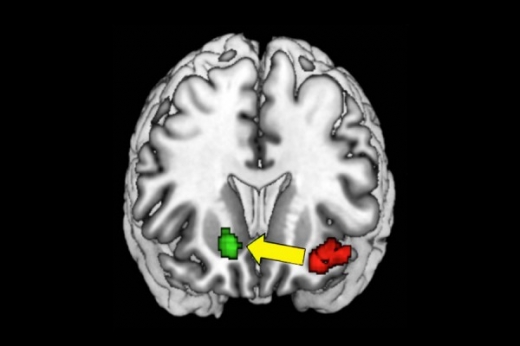

그때 자기공명영상장치(MRI)를 통해 뇌의 어느 부위가 활성화되는지 확인한 결과, 흔히 ‘보상회로’나 ‘쾌락중추’로 불리는 부위가 활성화하고 있는 것으로 나타났다. 이 부위는 복측피개영역(VTA, ventral tegmental area)와 전뇌 부분의 내측전전두엽(mPFC, medial prefrontal cortex), 그리고 중격측좌핵(NAc, nucleus accumbens) 등으로 연결되는 신경망을 말한다.

사진=ⓒ포토리아(위), 네이처 커뮤니케이션스